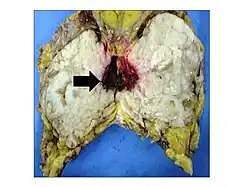

.jpg)

Malignant phyllodes tumors can behave similarly to sarcomas leading to development of blood-borne metastases.[16] Approximately 10% of phyllodes tumor develop distant metastases and this occurrence is higher (20%) in patients with histological-identified malignant tumors.[16] The most common site for distant metastases include the lung, bone, and abdominal viscera.[17] In more insidious cases, the parotid region has also been described in literature.[18]